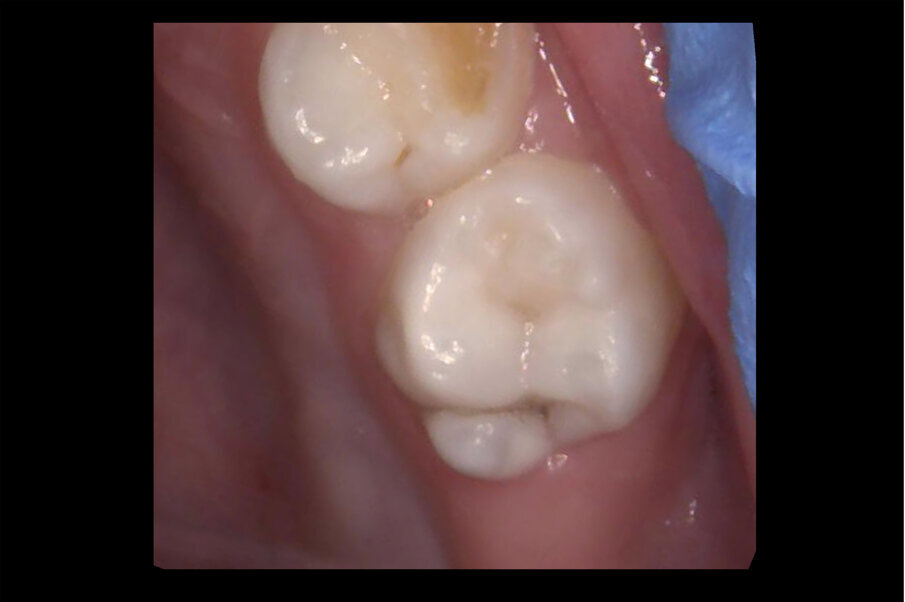

Afbeelding 1. Casus 1: 18-12-19. Kiespijn dreigt. ZDF aanbrengen veroorzaakte minutenlang pijn.

Afbeelding 2. Casus 1: 13-03-20. Na 4 maanden zwart verkleurd en symptoomvrij met vitale pulpa.